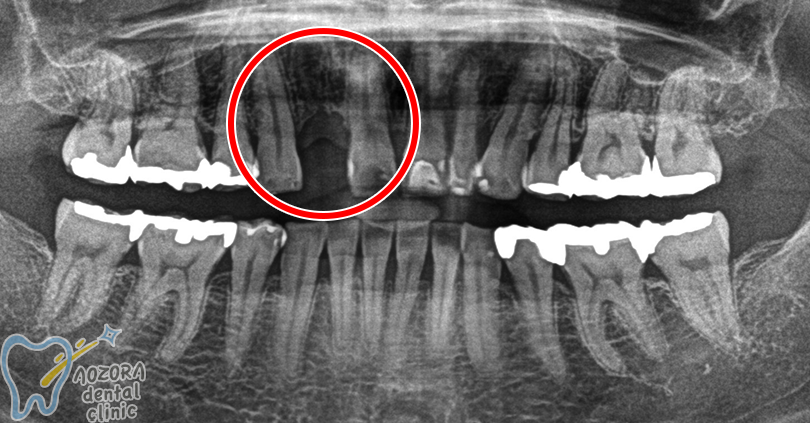

70歳 女性の場合

主訴

歯が折れて、残せなくなったため、インプラントを希望しました。

治療期間 6ヶ月

歯を抜いてから、骨ができるのに3ヶ月

それからOPEをしたため、約6ヶ月かかりました。

術前

術後